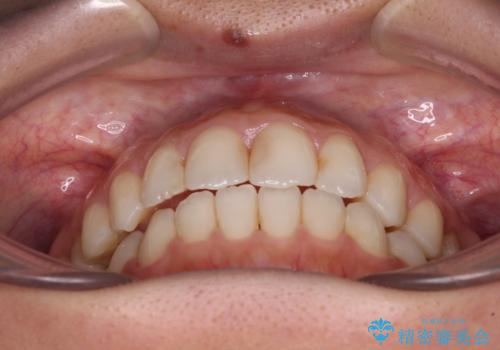

オープンバイトによる見た目を治したい インビザラインでの矯正治療

- オープンバイトのため、話しているときの見た目が気になるとのことで来院された患者様です。

下顎骨は左側にシフトしており、咬み合ったときには奥歯と前歯の一部しか接触していない状態でした。

骨格的な左右差は歯列矯正は改善できないため、上下歯列が全体的に接触することをゴールとしてインビザラインにて矯正治療を行うこととしました。

前歯のデコボコの解消と並行して上下の奥歯を圧下させるようにすることで、前歯を接触させるように計画しました。

上下の隙間に舌が入り込むことがオープンバイトの原因であったため、舌の筋肉のトレーニングも並行して行い、後戻りの抑制を図りました。